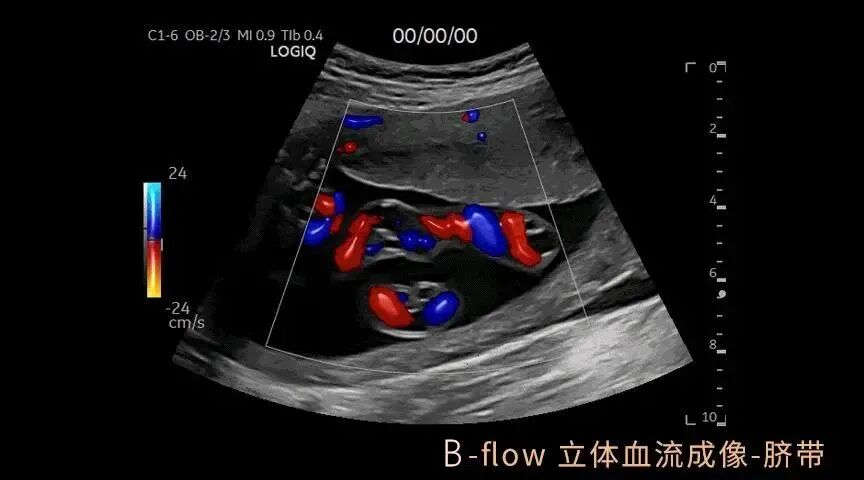

GE LOGIQ-Fortis Plus在甲状腺、乳腺、双下肢、颈部血管等检查项目方面有明显优势,对微血流的显示和弹性成像技术有全新的视野,图像更清晰细腻,血流显示立体逼真,能够实现二维条件下血流的“立体浮雕式”呈现,减少彩色血流闪烁,增强细微血管的可视化成像效果有利于临近交叉血管的边界识别。